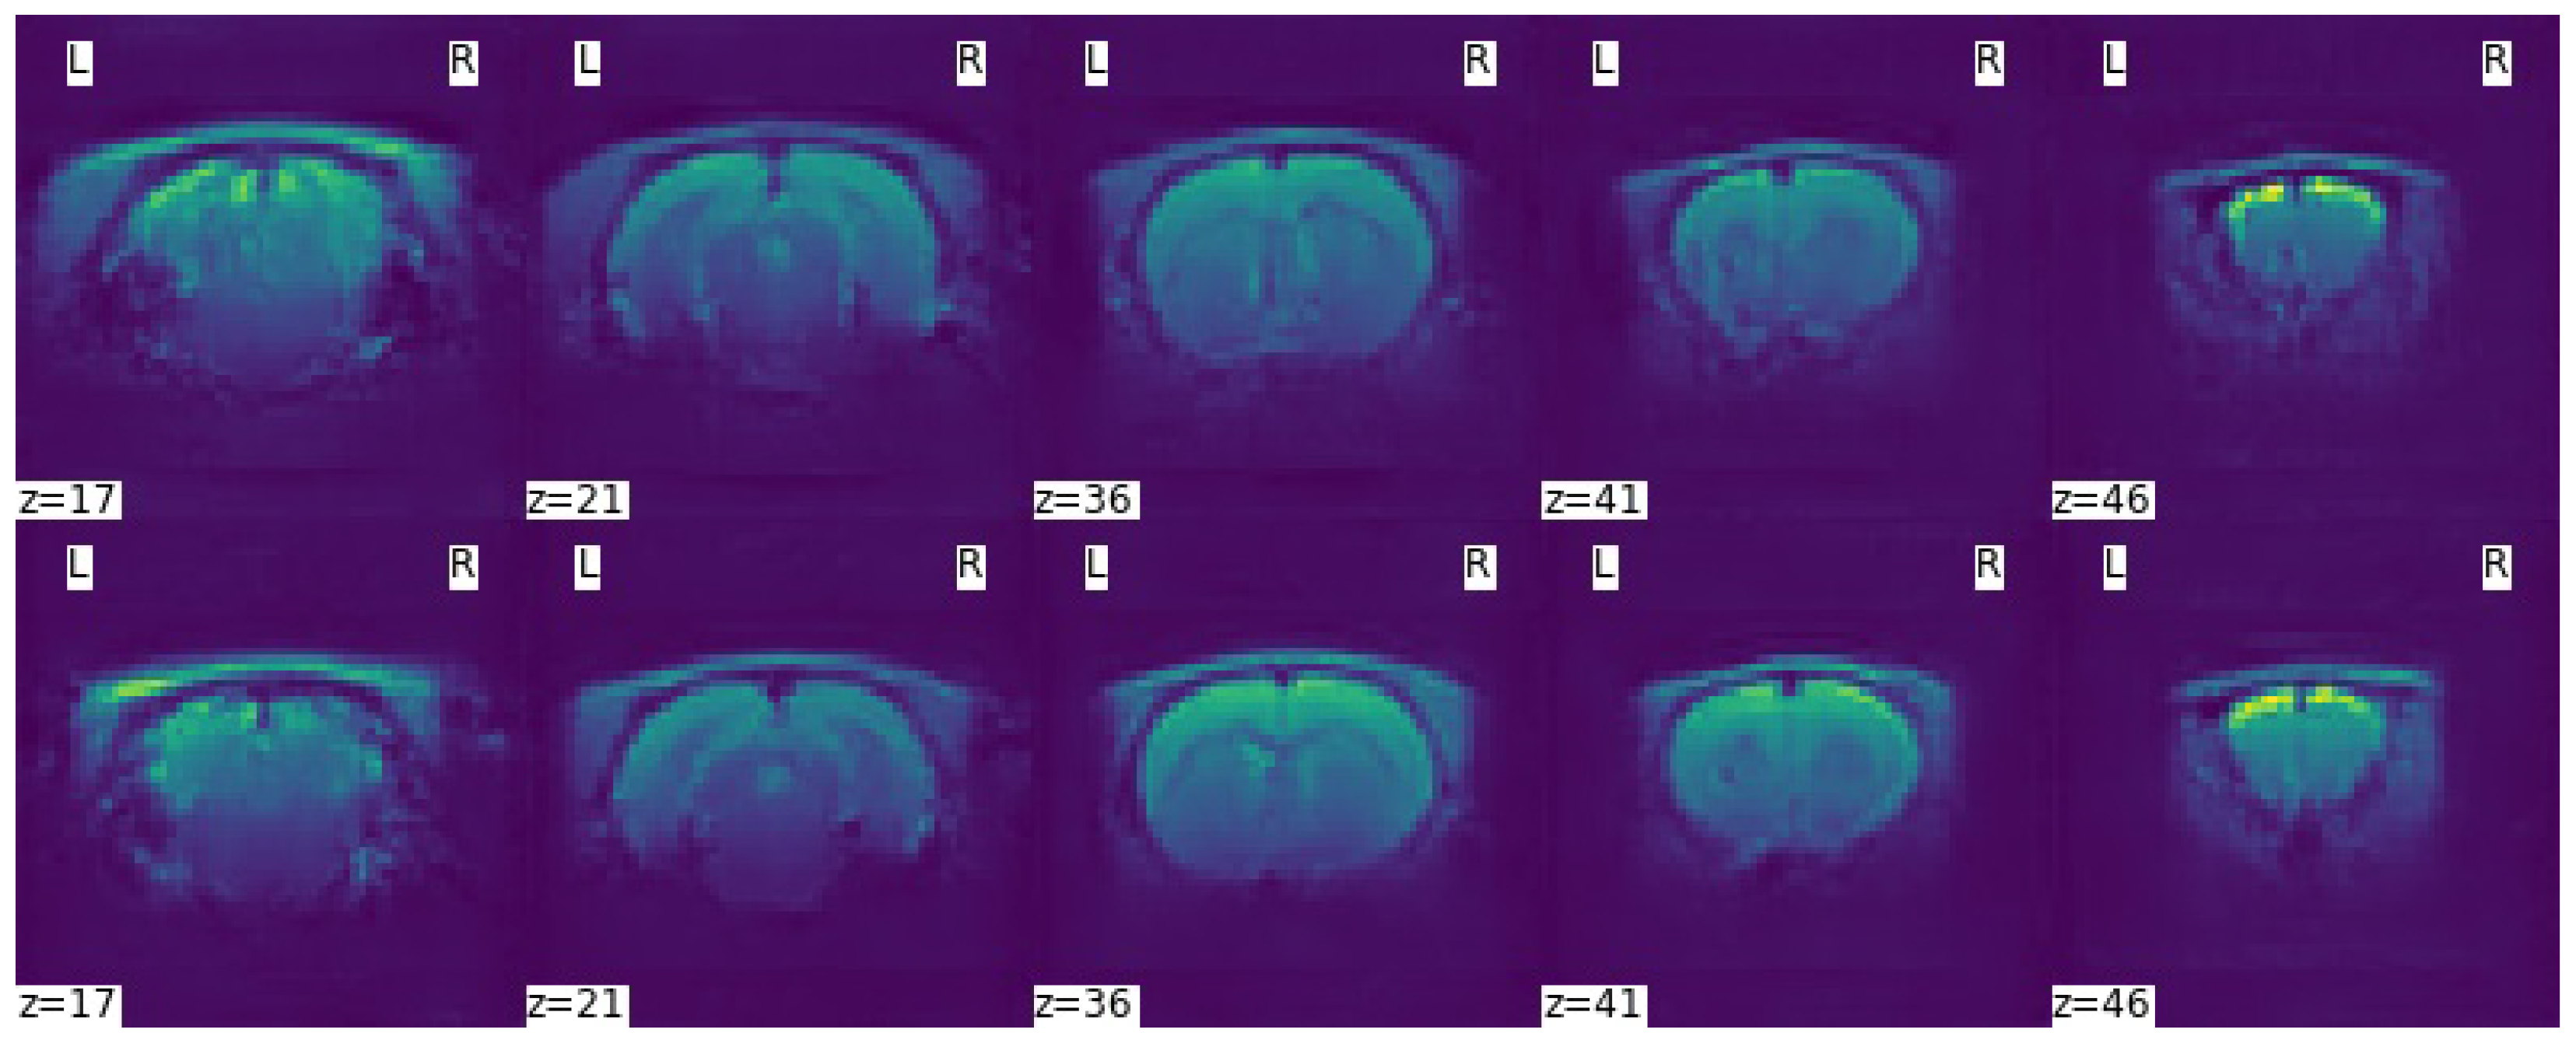

It is not good practice to compare different generative models using loss function diagrams, as they do not correspond to human perception. These diagrams are only a good tool to check for the presence of mode collapse, which is characterised by the divergence between the discriminator and the generator loss function diagrams, one tending to and the other to +∞. Normally, the training runs until this divergence occurs, but since an -GAN architecture with VAE was used, this would never happen or it would require many more iterations, so it was decided to run 200,000 iterations. Comparison of the scans generated after 100,000 and 200,000 training iterations confirmed that the learning process is not directly related to the representation of the loss functions. This can be seen in Figure 9 by the lack of detail in the generated scans after 100,000 training iterations—first row—and a significant improvement after 200,000 training iterations—second row.

Figure 9.

Axial slices of a generated scan with the -WGANSigmaRat2 model after 100,000 iterations (first row) and after 200,000 iterations (second row) of training. L and R refer to the left and right sides of the brain respectively.